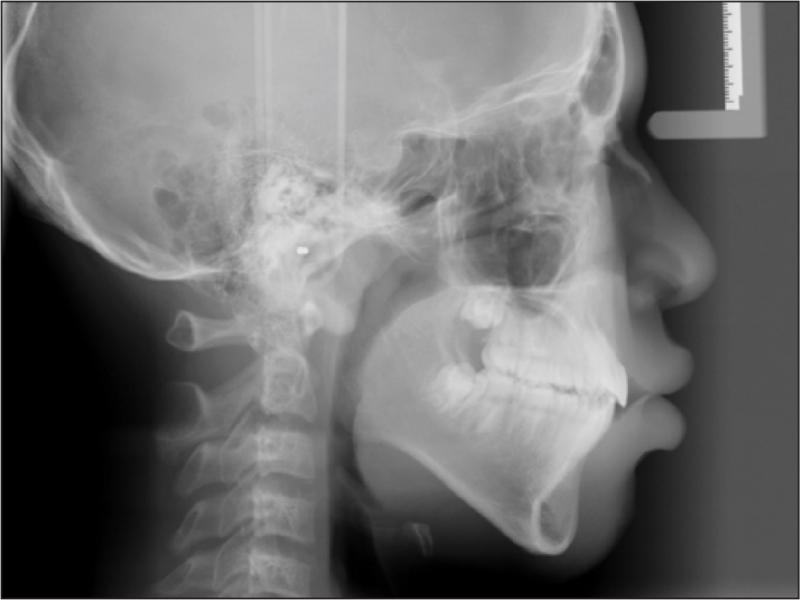

A 12-year-old African American male in good general health presented with the chief complaint of “I don’t like my upper front teeth”. An extra-oral examination revealed a convex soft tissue profile, an obtuse nasolabial angle, and lips that were protruded and incompetent. Upon intraoral examination, the patient had tooth staining, a retained deciduous upper left canine, a malformed upper right canine, a Class I molar relationship, spacing, an increased overjet and an anterior open bite (Figure 1). A radiographic examination revealed a congenitally missing upper left canine, an upper right permanent canine with a long root, an upper right first premolar with a short root, proclined and protruded upper and lower incisors and a high mandibular plane angle (Figures 2 and 3; Table I).

Lateral cephalogram taken at the initial visit (age 12 years, 0 months).